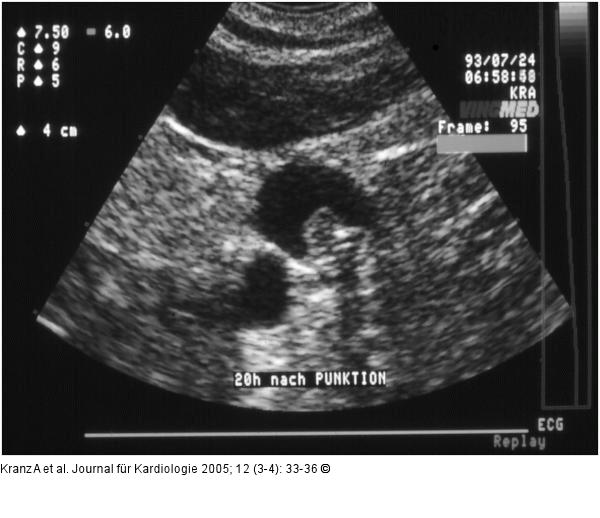

Abbildung 7: Katheterassoziierte Thrombose

Katheterassoziierte Thrombose der V. jugularis int. |